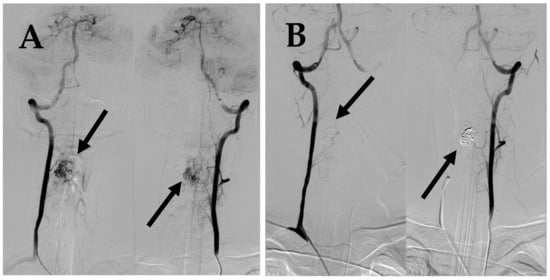

7.1. First Episode (2011)

7.2. Second Episode (2020)

7.3. Third Episode (2023)